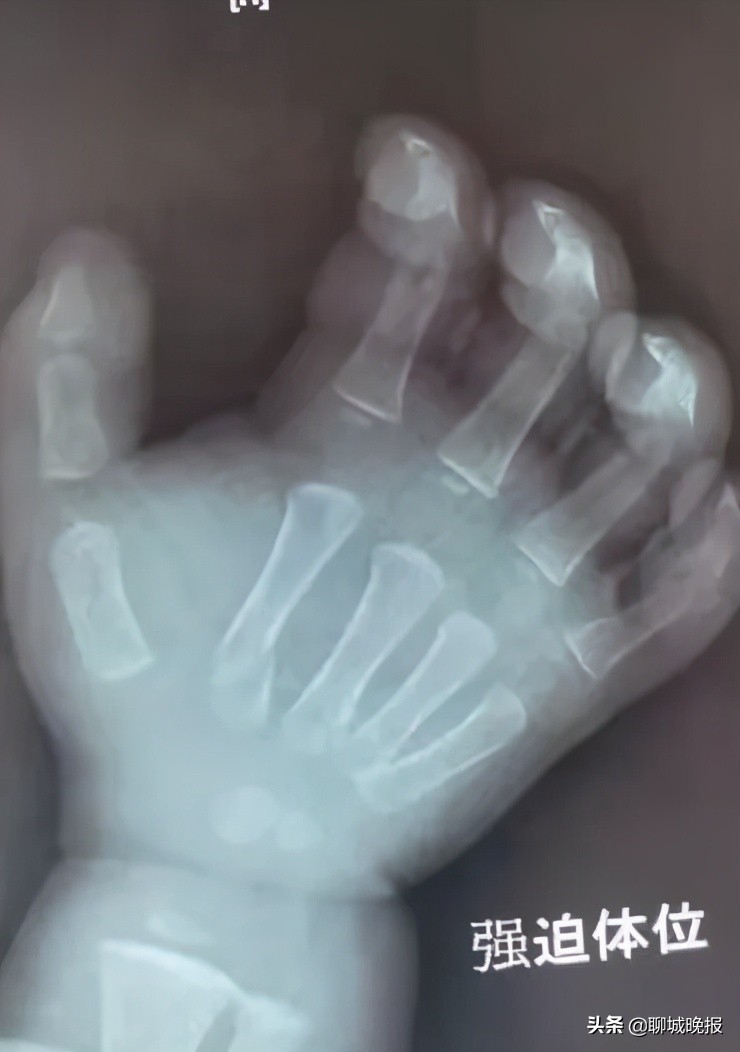

原来,3月4日下午,患儿在玩耍时看到转动的机器,非常好奇,趁大人一个不留意便伸手摸了上去,结果被绞伤导致右臂粉碎性骨折,遂来我院就医,诊断为右肱骨干粉碎性骨折,右尺桡骨骨折,右第2、3、5掌骨骨折。

术前 ↑ 术后 ↓ 对比